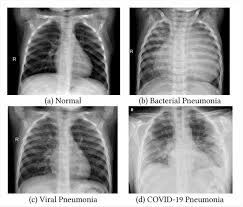

Pneumonia Vs Lung Cancer Symptoms In Dogs : Tracheobronchitis Bronchitis In Dogs Dog Owners Merck Veterinary Manual - This is a malignant neoplasm, with the ability to grow rapidly and metastasize to distant parts of the body, including the organs, lymph nodes, bones, brain and eyes.. When they do cough, they might bring up blood. Usually there are no symptoms in the early stages of canine lung cancer. Metastatic cancer to the lungs is much more common than primary lung cancer. When coughing may mean your dog has lung cancer. Read on and learn more about the symptoms, causes, and treatment of pneumonia in dogs.

The vet will look for nasal discharge, coughing, take the temperature of the dog, and listen to the lungs using a stethoscope. Severe symptoms in combination with poor appetite could. A veterinarian will perform a full physical examination on a dog after an owner notes symptoms that are characteristic of pneumonia. But in some rare cases, it may be a lung cancer (primary or secondary). Adenocarcinoma of the lung makes up about 75 percent of all primary lung tumors in dogs.

Types Treatments Symptoms Of Lung Cancer In Dogs Plains Veterinary Oncology Northeast Veterinary Referral Hospital from d2zp5xs5cp8zlg.cloudfront.net Lung cancer is sometimes found this way. Symptoms of lung cancer are coughing (which may also produce phlegm or blood), exercise intolerance (lethargy), weight loss or loss of appetite, and other respiratory signs such as trouble breathing or shortness of breath. Antibiotics may be prescribed to treat pneumonia. A veterinarian will perform a full physical examination on a dog after an owner notes symptoms that are characteristic of pneumonia. Usually, this is a sign of your dog's body fighting the infection, but if your dog overheats, it could be dangerous or even fatal. Some severely affected dogs may have extreme exercise intolerance. Sometimes, people with pneumonia may have symptoms similar to lung cancer. However, primary lung cancers are being seen more frequently over the last 20 years.

Just like pneumonia in people, pneumonia in dogs is a serious health condition and. Usually there are no symptoms in the early stages of canine lung cancer. There are times when coughing may mean your dog has lung cancer. Most primary lung tumors are diagnosed at an average age of 10 to 12 years in dogs. A veterinarian will perform a full physical examination on a dog after an owner notes symptoms that are characteristic of pneumonia. These signs are not specific for bronchitis and can also be seen with many other diseases including heart failure, pneumonia, allergic lung disease and lung cancer. Adenocarcinoma of the lung in dogs. It is characterized by a moist, bubbling cough and fever. However, primary lung cancers are being seen more frequently over the last 20 years. Some of the pneumonia symptoms overlap with those of the cold, but the condition also has discerning symptoms of its own. Primary lung tumors average cost. It usually results in mild symptoms, mild or no pneumonia, and it resolves within 5 to 7 days. Sometimes, people with pneumonia may have symptoms similar to lung cancer.

Chest X Ray For The Diagnosis Of Lung Cancer from www.verywellhealth.com There are many possible causes. Pneumonia is a common lung infection. However, primary lung cancers are being seen more frequently over the last 20 years. Pneumonia in people with lung cancer. The infection that causes pneumonia will often cause a high fever in dogs. Pneumonia can be mild and only require a week of treatment before you can. Specific signs will depend on where the tumor is located and may include a swollen paw, eye discharge or sores in the mouth. The vet will look for nasal discharge, coughing, take the temperature of the dog, and listen to the lungs using a stethoscope.

Kennel cough is the name given to a syndrome caused by viruses and bacteria. None of these symptoms are definitive on their own, as the signs of lung cancer can be similar to the signs seen in dogs suffering from other health conditions, like heart failure, pneumonia, or a heartworm infection. Pneumonia is an infection of lung tissue usually caused by viruses, bacteria, fungi, and/or parasites.however, bacteria and viruses cause the majority of pneumonia infections. The infection that causes pneumonia will often cause a high fever in dogs. There are many possible causes.

The cause can be bacteria, a virus, or fungi. Symptoms of primary and metastatic lung cancer are similar, although dogs with metastatic disease don't cough as much, according to the merck veterinary manual. It is also possible that a cancer diagnosis can be delayed if the cancer is mistaken for pneumonia. Unlike some other types of cancer, there are some concerning symptoms that arise in the earlier stages of primary lung cancer for dogs that should immediately alert you that something is wrong. Most primary lung tumors are diagnosed at an average age of 10 to 12 years in dogs. When they do cough, they might bring up blood. Pneumonia in people with lung cancer. It is caused by a viral or bacterial infection in the respiratory tract. Primary lung tumors average cost. Lung cancer is sometimes found this way. Canine distemper virus, adenovirus types 1 and 2, canine influenza virus, and. Some of the symptoms may include: Some of the pneumonia symptoms overlap with those of the cold, but the condition also has discerning symptoms of its own.